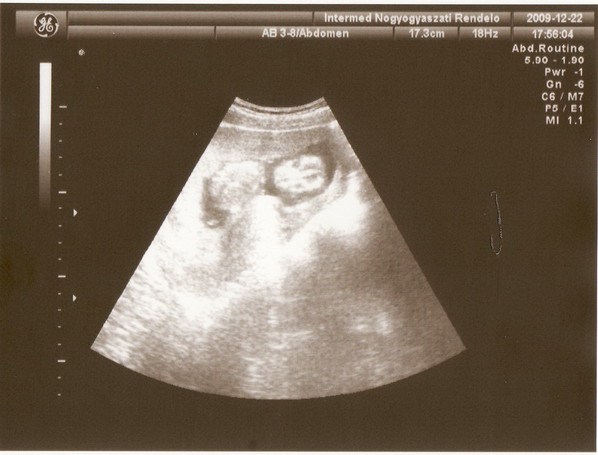

Detti, nagyon jok ezek a kepek! Hat ahogy mondtam - es most megerodotem a multkori elkepzelesemben - engem nem 4Dvel nezett a dokineni amikor megmondta a tutit, hogy a gyerek neme fiu :) Ilyen vagy hasonlo terbeli kepeket en nem lattam (pedig a gepen volt 4D opcio, azt lattam).

Detti, gyönyörű a kiscsaj! A 4D genezist én is csak ajánlani tudom, Andrissal voltam legalább 3 helyen, de messze ez a legeslegjobb......itt rögtön anyukánaK érzed magad, valószínű mindenkit ugyanúgy dicsérgetnek, de az teljesen mindegy, érzed a törődést!!!!!!

Mindenkinek köszönöm szépen a dícséretet, olvadozok tőle rendesen. Luna: ezen a gépen is úgy volt, h kapcsolgatta 2 és 4D között, és pont a nemét nekem is sima 2D-s felvétel alapján mondta meg. De annyira biztos volt benne, hogy most néztem meg a hazahozott filmet, és rajta is a felirat azon a részen, hogy "kislányunk" - én ugyan most sem látom. Valóban jó volt ez a hely, sztem árban is, 10.500.-Ft-ért 1 órás nézegetés, majd elaludtam az ágyon, annyira klassz volt a halk zene és a mozi... a szonográfus kiemelt részeket, pl.a talpa, meg egyik képen a kis kézfeje úgy áll, mintha intene a baba, ráírta a képkockára, hogy h "hello", és ilyen kis apróságok egy kezdő kismamának maga az álmok netovábbja, hihetetlenül viccesnek találtam, pedig nem vagyok ám annyira infantilus. :) :)

nekem nagyon tetszik mind a két kép, a 2.on olyan, mintha egy koncerten lenne :P

A kis csillagommal minden rendben, kb10 cm és 85g. A nemét persze még titkolja :x :P

és született a kis ufóról egy nem túl előnyös fotó :D

Kép itt figyel minket :-)

Geoo, nagyon édi a babád, sztem nem is előnytelen a fotó :) majd kiváncsi leszek a Ti 4D-tekre is, biztosan kiderül a neme, s azt is várom, hogy onnan milyen képet hozol majd :)